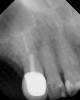

Figure 3  Buccal and radiographic views of posterior edentulism with significant sinus pneumatization in the molar region.

Figure 3